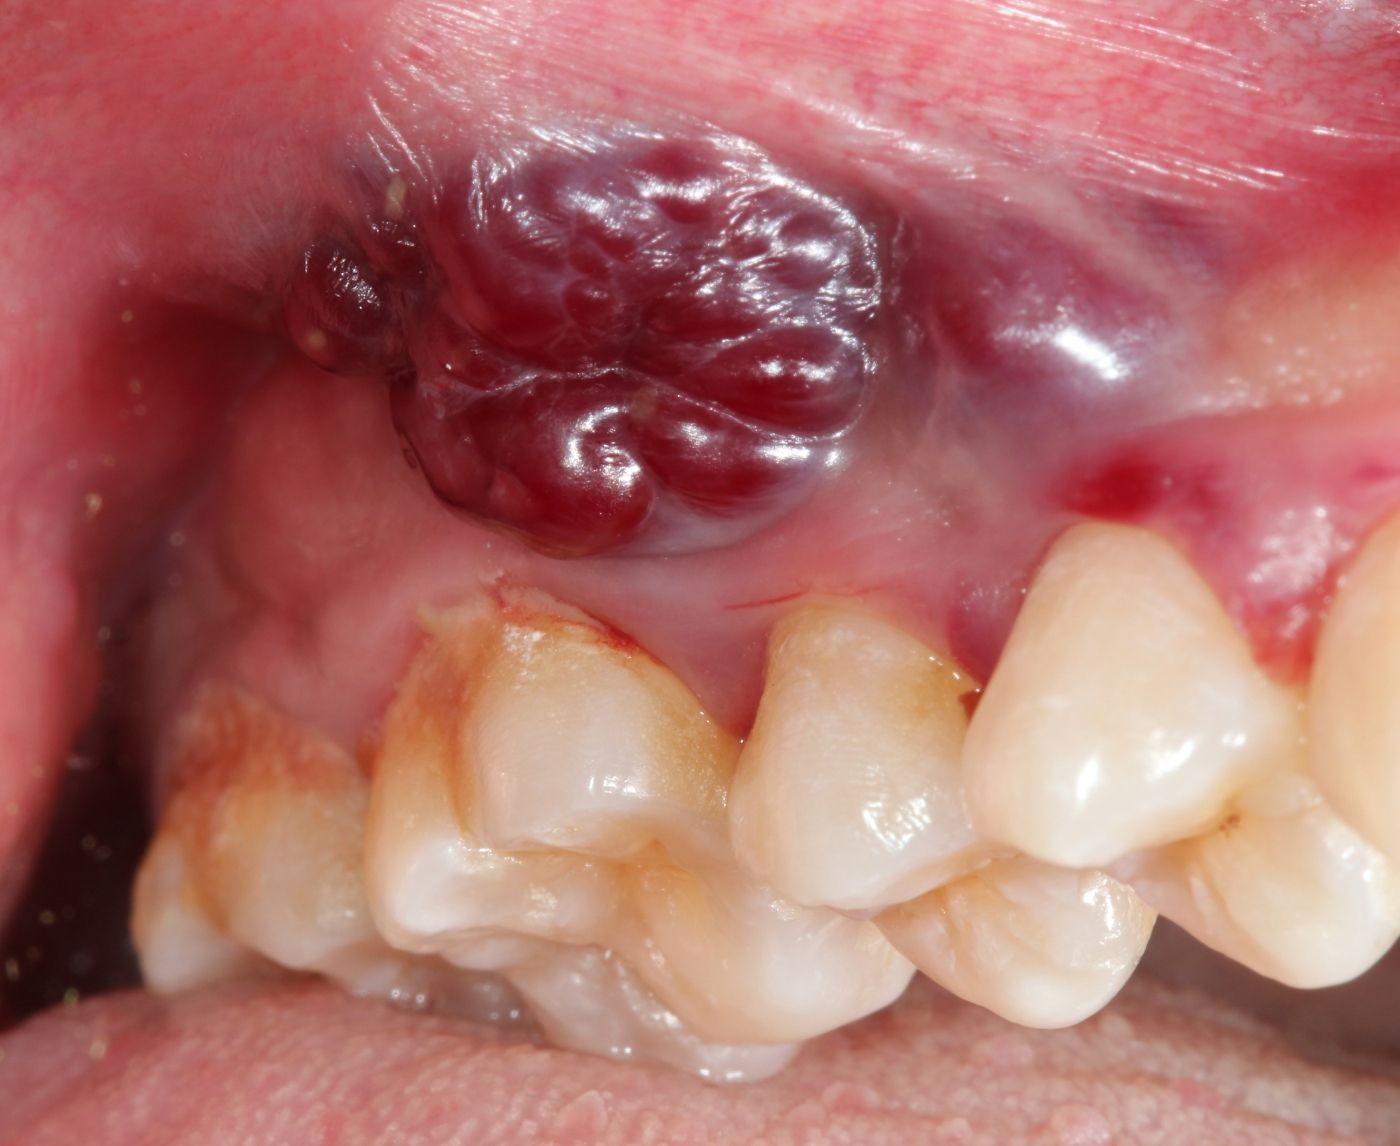

3. What does an oral STD look like, or feel like?

Some people have sore throats, redness, or tiny sores, but many oral STDs are symptom-free. That's why you should get tested regularly.